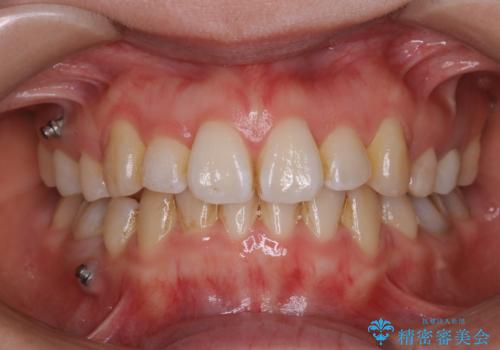

[ セラミック治療 ] 前歯を自然にしたい、セラミッククラウンのやりかえ

担当医 大元洋佑

![[ セラミック治療 ] 前歯を自然にしたい、セラミッククラウンのやりかえの症例 治療前](https://seimitsushinbi.jp/wp/wp-content/uploads/2022/02/771f39d281c5095ad94cbf96f730d007-500x350.jpg?v=1644041614)

![[ セラミック治療 ] 前歯を自然にしたい、セラミッククラウンのやりかえの症例 治療後](https://seimitsushinbi.jp/wp/wp-content/uploads/2022/02/b9ee13367ab56d7729121dc9c683836d-500x350.jpg?v=1644041633)